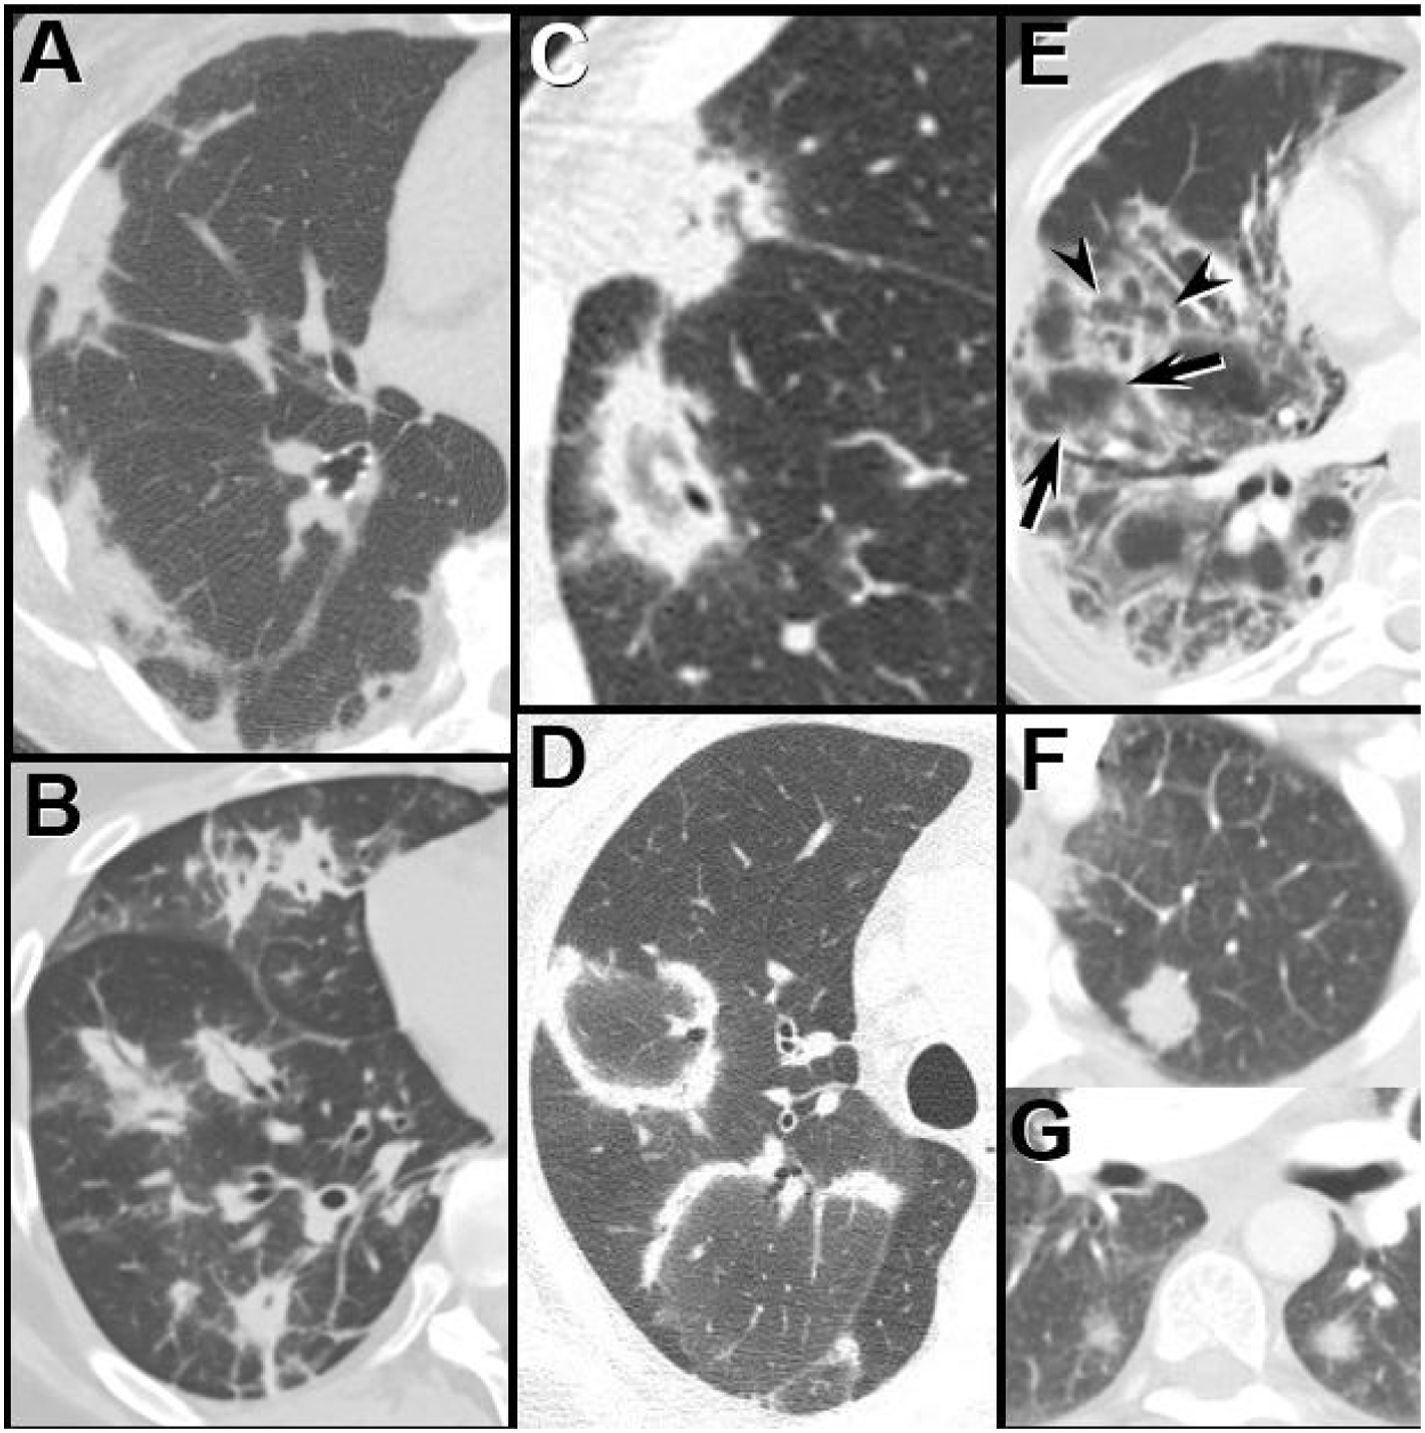

Three CT imaging findings described by Chung et al., 25 suggest the diagnosis of CTD-associated UIP over IPF-associated UIP: the exuberant honeycombing sign, the anterior upper lobe sign, and the straight -edge sign (Fig. 2). While the sensitivity of each sign was low, the specificity for each approximates 87%. The authors suggest that when all 3 signs are present a thorough workup for CTD-ILD should be pursued, including referral to the rheumatology department.77

The UIP pattern: HRCT features favoring a connective tissue-associated etiology from IPF.25 (A) The “exuberant honeycombing” sign-cyst formation constituting greater than 70% of the fibrotic portions of the lung. Prone HRCT image in a patient with RA shows a UIP pattern with extensive basal honeycombing; compare with the definite UIP pattern at HRCT in an IPF patient (B). (C) The “anterior upper lobe sign”. Axial HRCT image through the upper lungs in a patient with RA shows concentrated fibrotic change with honeycombing; compare with the typical appearance of fibrotic change in the upper lobes in a patient with IPF (D). (E) The “straight-edge” sign. Coronal CT image in a patient with RA shows comparatively isolated extensive honeycombing and fibrotic change in the bases, showing a sharp demarcation in the craniocaudal plane (between arrowheads), and lack of substantial extension along the lateral pulmonary parenchyma cranially. Compare with coronal CT in a patient with IPF (F), which shows peripheral and basal predominant fibrotic lung disease, but with relatively greater lateral mid and upper lobe involvement (arrows).

By far, the most common CTD associated with UIP pattern is RA, present in 56–61% of patients.78,79 The UIP pattern is not limited to RA-almost any CTD, including systemic sclerosis, mixed CTD, myositis, and Sjogren, can exhibit a UIP pattern in a minority of cases. Furthermore, RA can also exhibit other ILD patterns, including NSIP (33%) and OP (11%), as well as serositis, nodules, and obstructive airway disease.